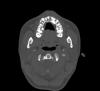

persona Опубликовано 12 октября, 2008 Поделиться Опубликовано 12 октября, 2008 (изменено) Здравствуйте.Хочу спросить совета у специалистов.Мне 25 лет. Решил разобраться со своими кривыми зубами. Пытался и раньше, но то, что мне сделали с помощью обычной пластинки еще в школьные годы, уже давно разъехалось в разные стороны. Мой случай в чем то, наверное, похож на вот этот:http://forum.stom.ru/index.php?showtopic=3286, только у меня все еще более запущено.Основная проблема в том, что у меня не вырос левый клык. Он остался внутри и лежит горизонтально. В результате, все верхние резцы съехали на свободное место, появились большие щели. Левая двойка даже умудрилась заехать за нижний клык. На нижней челюсти зубы скученны, что конечно тоже хотелось бы исправить. Был у разных врачей. Насколько я понял, в моем случае желательно использовать брэкеты Damon. Предлагают две стратегии лечения:1) Освобождать место в зоне невышедшего клыка, а затем либо вытягивать его (что маловероятно), либо удалять клык и вставлять имплант на это место. При этом верхние резцы выдвинутся немного вперед и, соответственно, освободится место для выправления нижних зубов без удаления.2) Невышедший клык не трогаем, на его место смещается 4-ка, которая и будет исполнять роль этого клыка. Верхние зубы смещаются к центру, а нижние выпрямляются с удалением левой 4-ки. Последний из посещенных мною врачей как раз предлагает 2-ой подход, а про 1-ый говорит, что на такое лечение уйдет больше времени + придется удалять невышедший клык, без чего можно вполне обойтись + с недоверием относится к выдвижению верхних зубов + наверняка придется удалять какие-то 8-ки + выглядеть все в итоге будет примерно также. Но врач, который предлагал 1-ый способ, тоже вроде опытный специалист, так что я не знаю, кому из них больше доверять. Прошу знающих людей помочь мне определиться с методом лечения, да и вообще поделиться какими-то своими соображениями по поводу моего случая. Выкладываю фотографии и панорамный снимок. На фото верхней челюсти не жвачка , а временная пломба - сейчас как раз прохожу лечение у стоматолога, так что не обращайте внимание. Изменено 12 октября, 2008 пользователем persona Ссылка на комментарий

persona Опубликовано 12 октября, 2008 Автор Поделиться Опубликовано 12 октября, 2008 (изменено) Кроме того, проходил КТ. Выкладываю несколько срезов в области клыка. Изменено 12 октября, 2008 пользователем persona Ссылка на комментарий